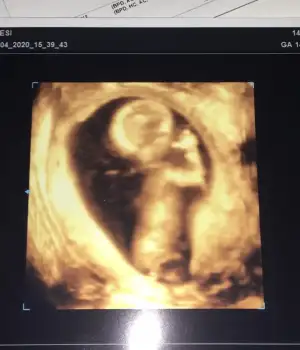

Nubu görünmüyor ama şekli şemali kız 10 haftalıkta kızoda bu![]()

dr 100/80 kız dedi ikinci bu ilk kızımda 4 yaşında şuanNubu görünmüyor ama şekli şemali kız 10 haftalıkta kızilk bebekmi